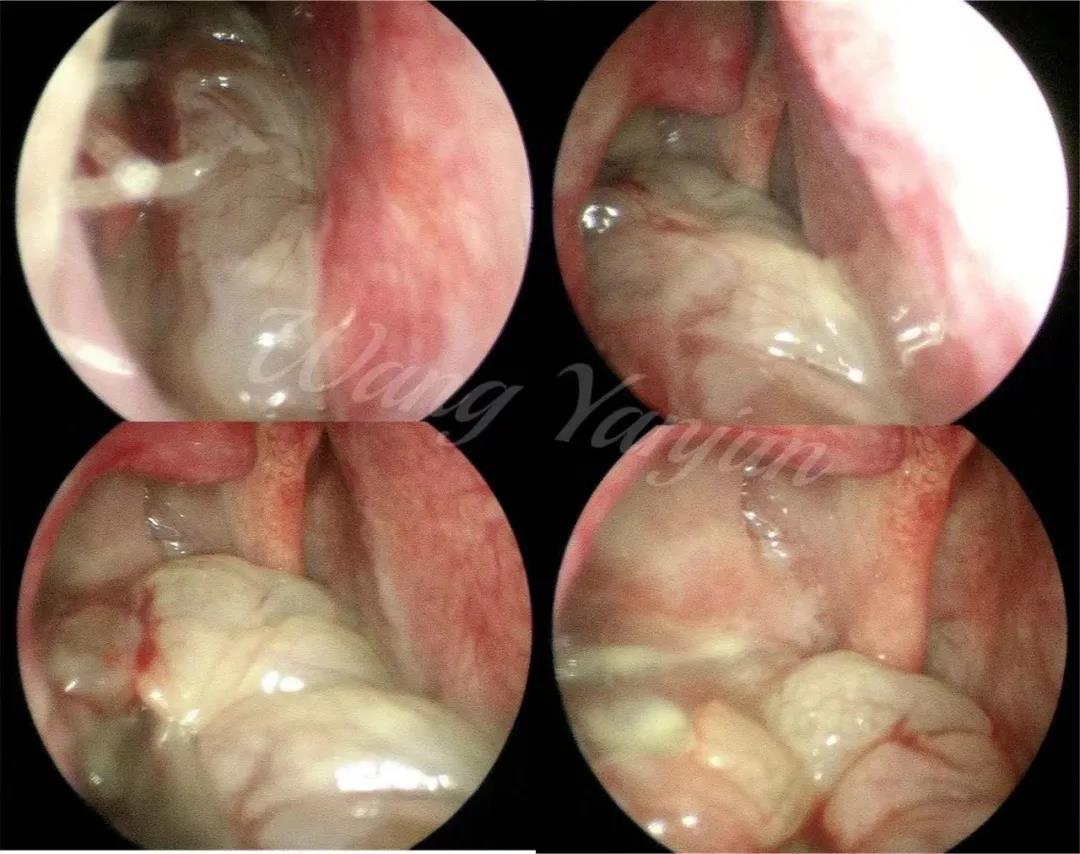

鼻内镜下右侧上颌窦内翻性乳头状瘤切除手术过程图

鼻内镜下检查可见外观呈息肉样或成分叶状,粉红或灰红色,表面不平,触之易出血。鼻窦CT检查表现为单侧鼻窦软组织密度影,鼻腔外侧壁可有骨质破坏,鼻窦间隔模糊。

当前,鼻腔鼻窦内翻性乳头状瘤以鼻内镜手术为主,根部肿瘤位置,部分患者需同时配合眉弓入路等外切口。手术方式和入路的选择根据肿瘤所在位置和肿瘤根基部来定,比如:位于上颌窦的肿瘤,肿瘤根基部位于上颌窦前壁时需要泪前隐窝入路,如果肿瘤位于内侧壁可选择保留或者不保留鼻泪管及下鼻甲的鼻腔外侧壁切除手术。